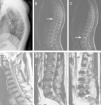

(A–C) A 5-year-old children with atypical spinal TB. (A) Lateral cervical vertebra radiograph showed bone destruction and osteopenia of the C4 vertebral body. (B) CT scan showed irregular lesions at the C4 vertebral body and swelling in paravertebral soft tissues. (C) C4 vertebral body had high signal on the T2-weighted image and the involved vertebral body was osteolysis or wedging. (D–F) A 60-year-old woman with atypical spinal TB. (D) Lateral lumbar spine radiograph showed T11 was slightly wedging. (E), (F) MRI showed an isolated slightly concentric collapse of the T11 vertebral body. The adjoining disk spaces were preserved.